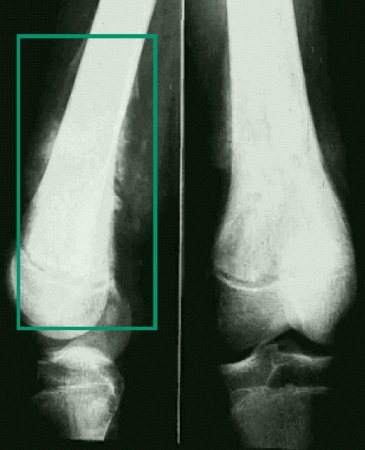

Doença maligna (leucemia, linfoma, tumor ósseo primário)[Figure caption and citation for the preceding image starts]: Tumor ósseo maligno (radiografia)Do acervo pessoal de Dr. Foster; usado com permissão [Citation ends].